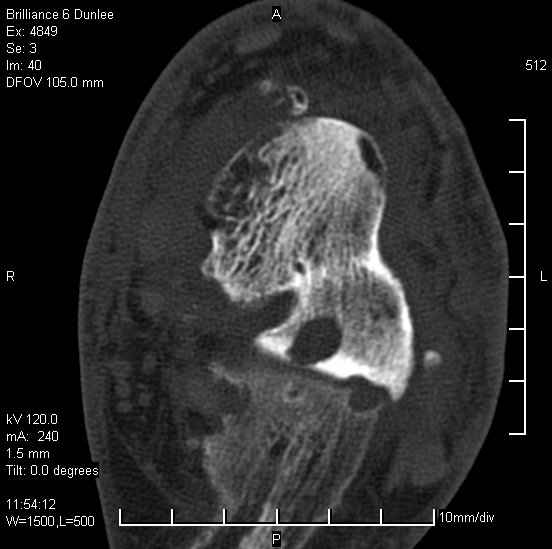

На лечении находится пациент 35 лет. Травма в сентябре 2008 г.- открытый вывих таранной кости

В день травмы ПХО, вправление вывиха, трансартикулярная фиксация. Рана зажила первично. С января нагрузка на конечность. С конца апреля- болевой синдром. На рентгенограммах и КТ признаки ас. некроза таранной кости, артроз подтаранного и голеностопного суставов.